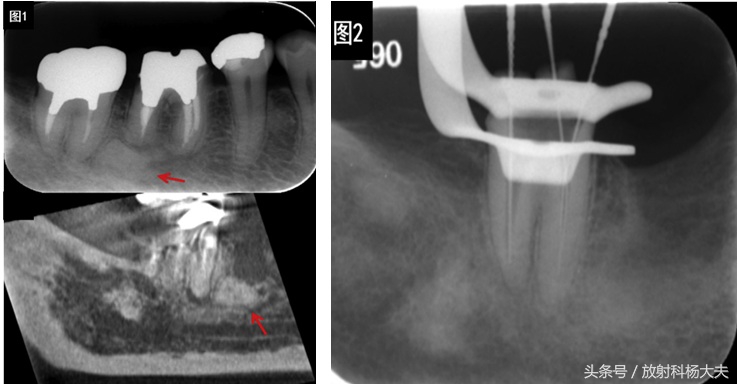

这半年起又断断续续听他念叨治疗经历,先是拔了这颗牙,可是疼痛并没有缓解。然后医生回顾牙片,发现第一磨牙根尖下有个小东西(图1所示),推测可能是疼痛的真正凶手,于是把它切除了,万幸是个良性的小东西,万万不幸的是疼痛丝毫没有改变。在医生的建议下,老王又战略转移至牙体牙髓科,医生根据牙片中根尖周围透过度的改变判断了牙髓炎症的存在(图1所示),于是又进行了多次根管治疗,可喜的是影像资料显示治疗后周围炎症有吸收缓解(图2所示),可不喜的是疼痛并没有随之改善。

上图所示红色箭头为右侧听神经鞘瘤,绿色箭头所示为水平走行的左侧正常听神经。